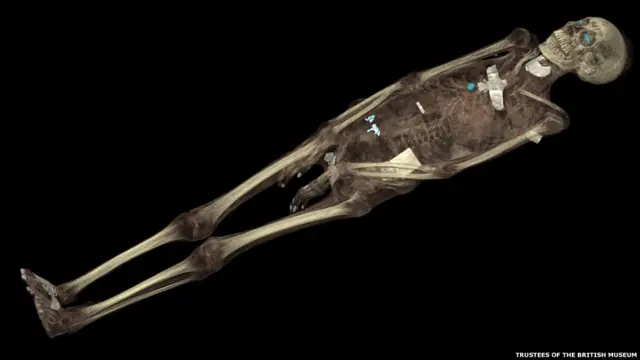

Новая экспозиция в Британском музее с помощью самых передовых технологий дает зрителю шанс заглянуть в прошлое и прикоснуться к жизни древних египтян.